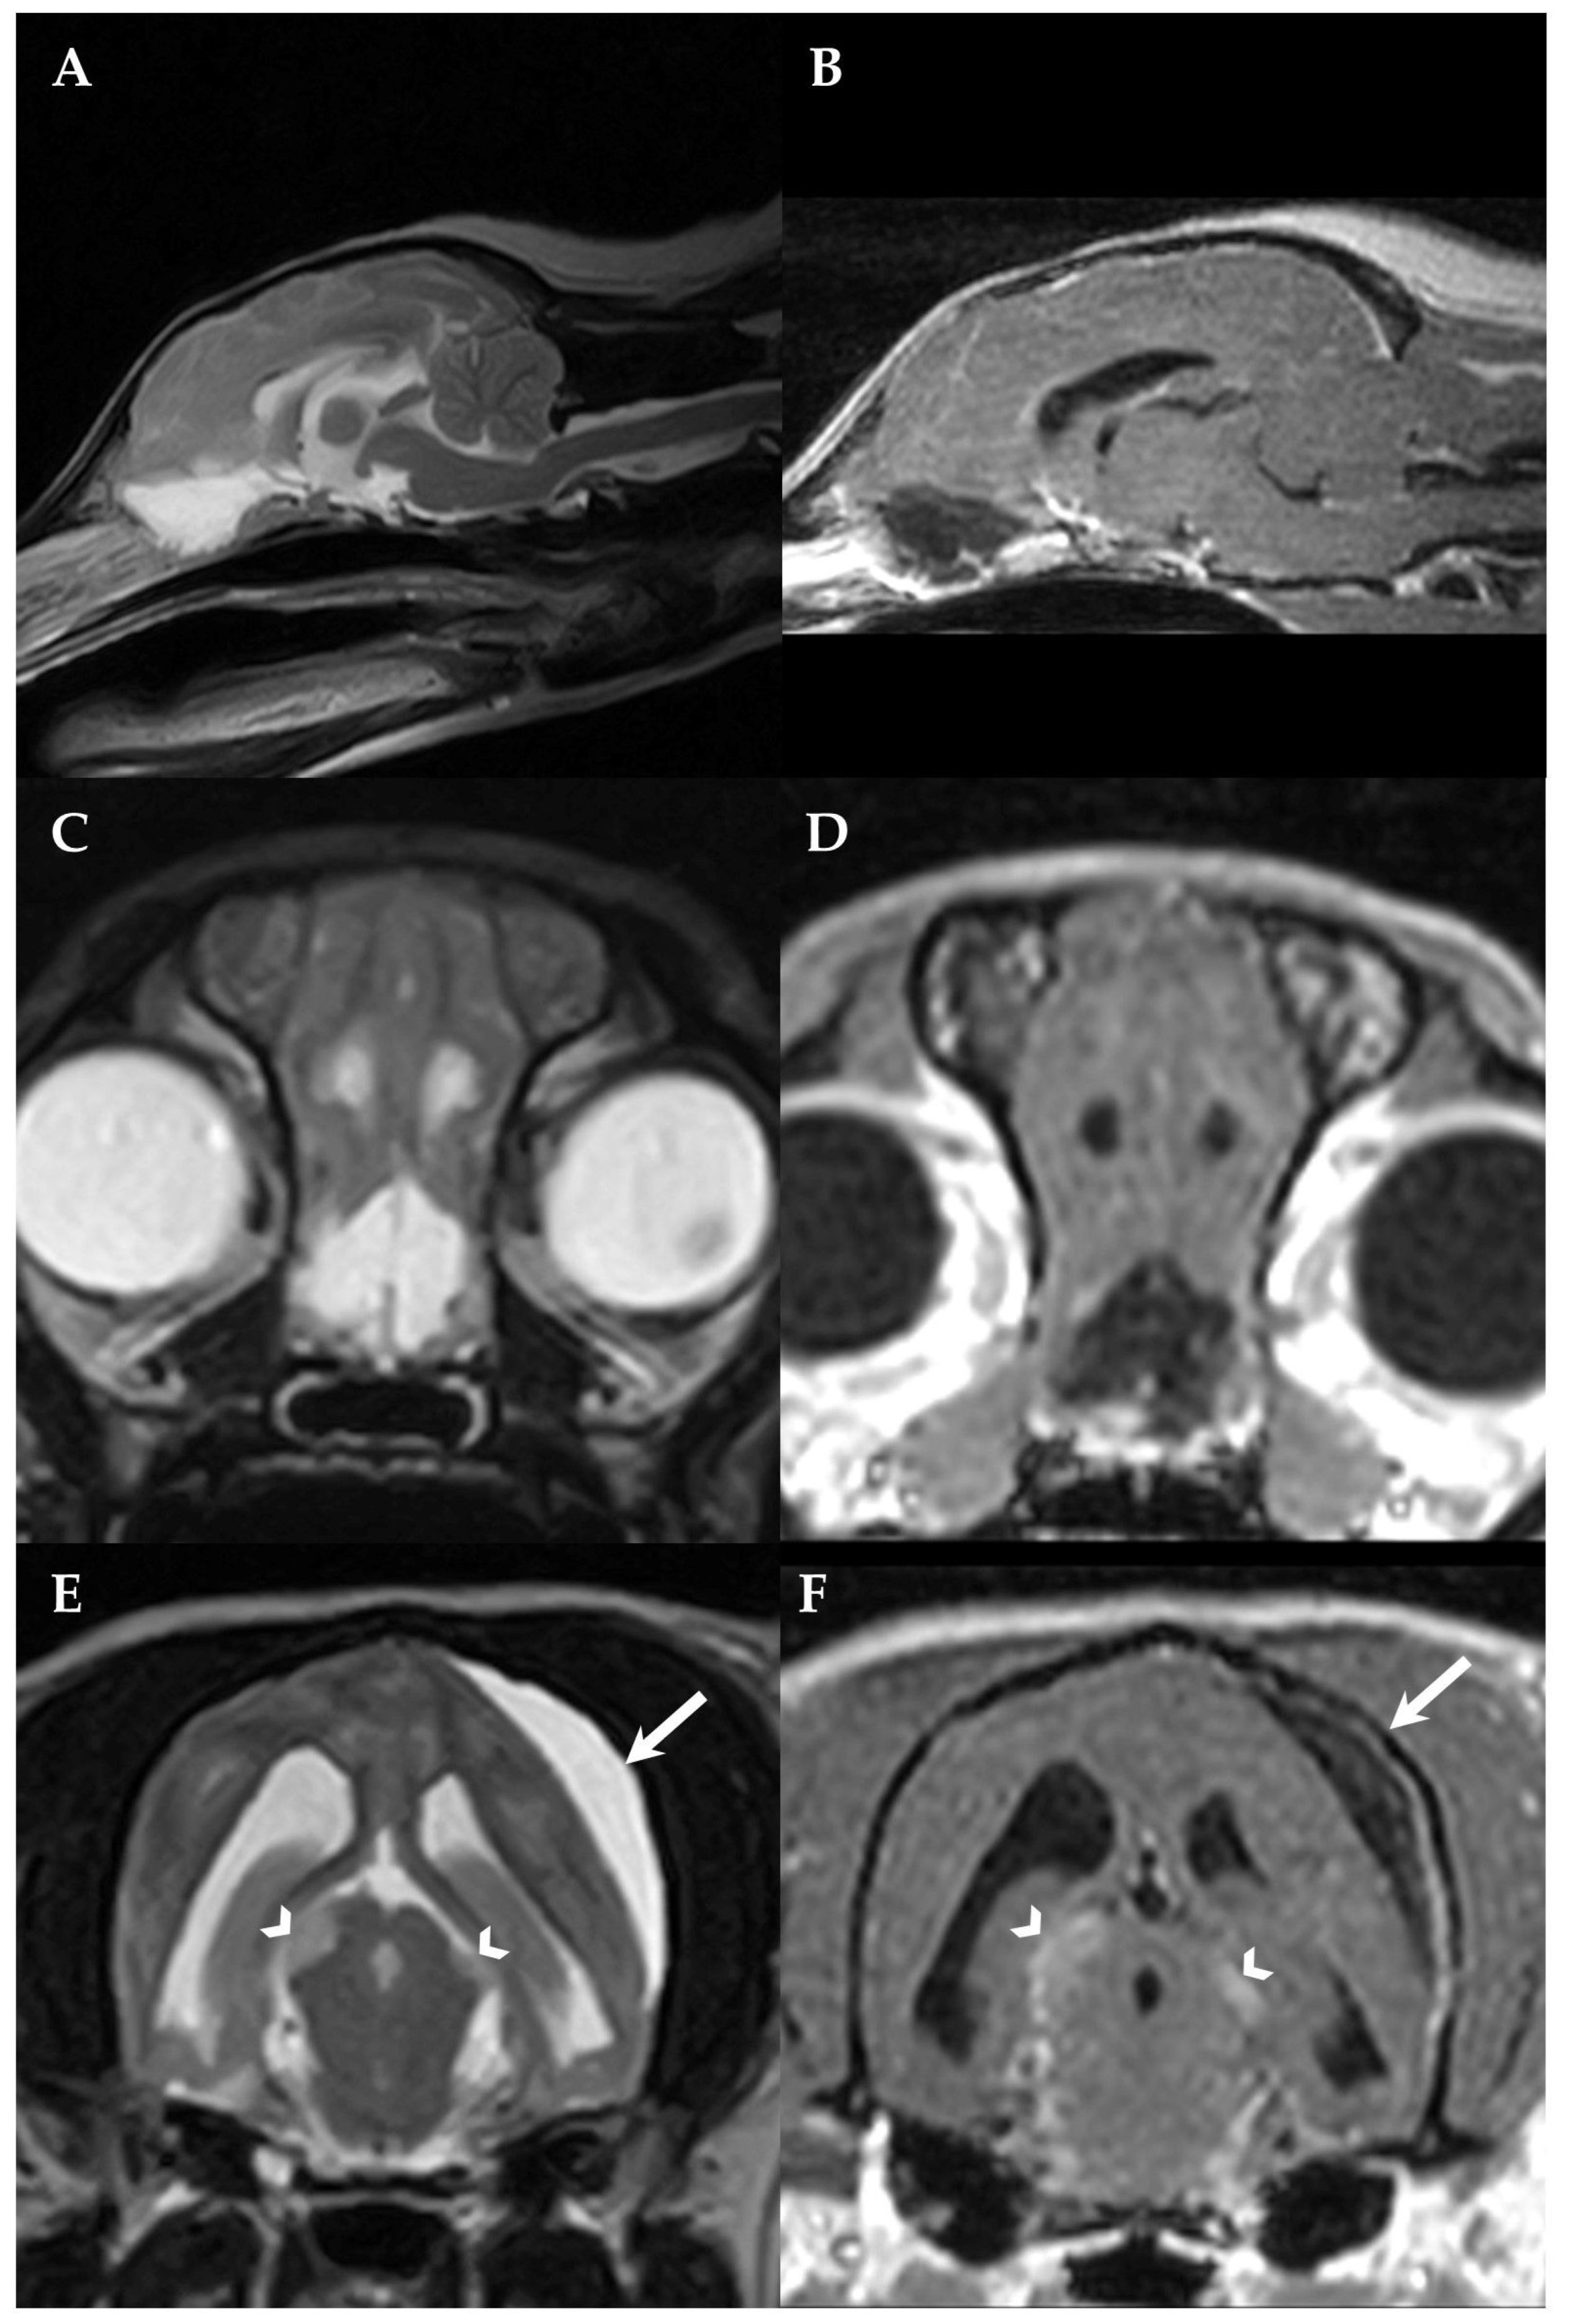

Figure 2.

First MRI of the dog´s brain. Sagittal T2W(A), sagittal 3DT1W after contrast administration (B), transversal T2W (C) and transversal 3DT1W after contrast administration (D) at the level of the olfactory bulb, transversal T2W (E) and transversal 3DT1W after contrast administration (F) at the level of the midbrain. Bilateral cyst-like lesions within the olfactory bulb and frontal lobe (A–D) as well as T2W hyperintense (E) and contrast-enhancing (F) asymmetrical midbrain lesions were identified (arrowheads). The SFA (arrows) can also be recognized, compressing the left parietotemporal lobe (E,F). Note the mild generalized meningeal enhancement and thickening (B,D,F). The left side of the patient is on the right side of the image.

Additional intra-axial, thin-walled, T2W hyperintense, 3DT1W and FLAIR hypointense lesions were noted within the olfactory bulb and the frontal lobe which were surrounded by T2W and FLAIR hyperintensities consistent with perilesional oedema (Figure 2A–D). Multiple ill-defined supposed intra-axial T2W hyperintense, 3DT1W iso- to hypointense and moderately contrast-enhancing lesions were recognized bilateral asymmetrically affecting the tectum mesencephali with a diameter of 6 × 3 mm on the right and 4 × 2 mm on the left side (Figure 2E,F) and mildly contrast-enhancing 4 × 3 mm lesions within the left lateral geniculate nucleus. A mild generalized meningeal enhancement and a mild, multifocal meningeal thickening were also recognized (Figure 2B,D,F).